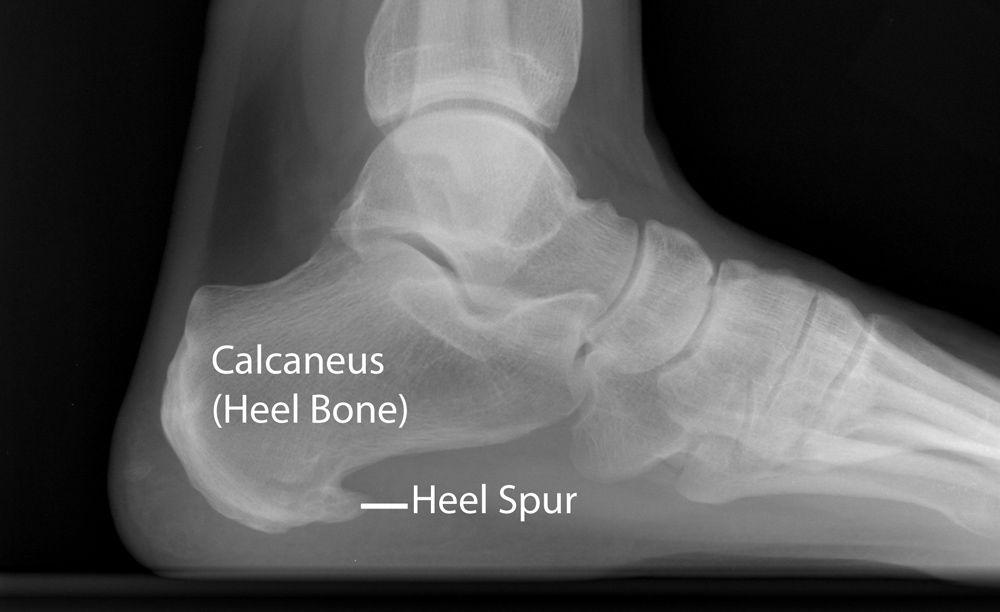

Calcaneal Spur Xray Plantar Heel Spur Icd 10 A bony outgrowth on the lower surface of the calcaneus. A calcaneal spur (or heel spur) is a small osteophyte (bone spur) located on the calcaneus (heel bone). The icd code m773 is used to code calcaneal spur a calcaneal spur (or heel spur) is a small osteophyte (bone spur) located on the. Plantar fasciitis uses the diagnostic code m72.2.. Plantar Heel Spur Icd 10.